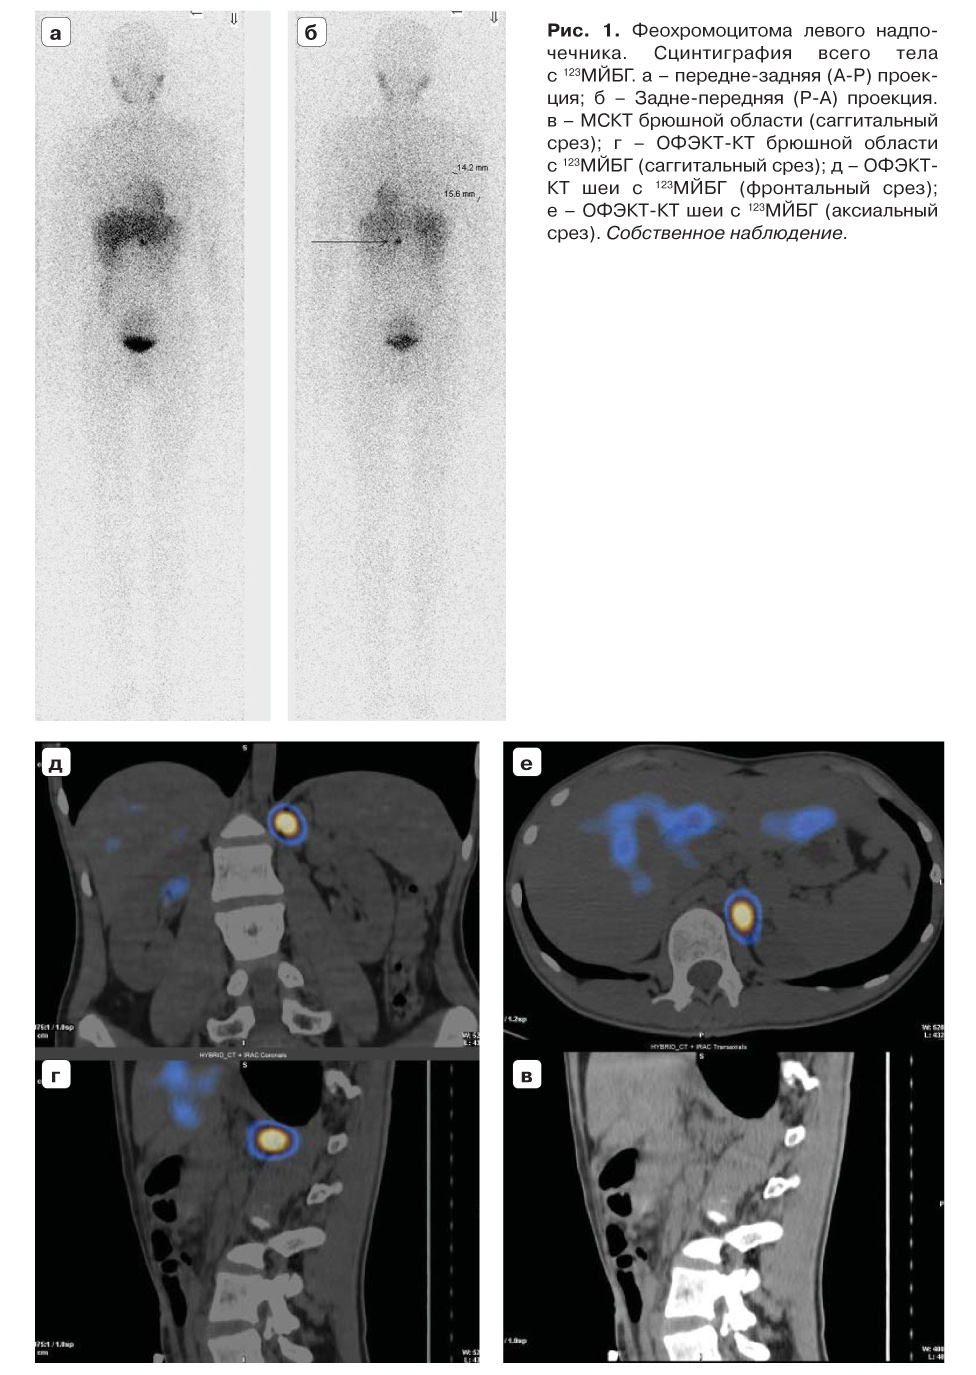

Для топической молекулярной визуализации параганглиом и феохромоцитом используется ОФЭКТ/КТ с 123I-МЙБГ. На рис. 1 демонстрируется собственный клинический случай феохромоцитомы левого надпочечника. На рис. 2 и 3 представленные собственные клинические случаи с локализацией опухоли на шее и в мочевом пузыре (встречается редко), соответственно.

Рис. 1. Феохромоцитома левого надпо- чечника. Сцинтиграфия всего тела с 123МЙБГ. а – передне-задняя (A-P) проек- ция; б – Задне-передняя (P-A) проекция. в – МСКТ брюшной области (саггитальный срез); г – ОФЭКТ-КТ брюшной области с 123МЙБГ (саггитальный срез); д – ОФЭКТ- КТ шеи с 123МЙБГ (фронтальный срез); е – ОФЭКТ-КТ шеи с 123МЙБГ (аксиальный срез). Собственное наблюдение.